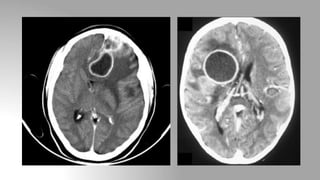

Ischemic stroke

1. Immediate phase (<1 hour): The earliest CT sign visible is a

hyperdense segment of a vessel, representing direct visualisation of

the intravascular thrombus / embolus and as such is visible

immediately

2. Early phase (1-3 hours): Loss of grey-white matter differentiation

and Hypo-attenuation of deep nuclei

3. First week: Hypo-attenuation and swelling become more marked

resulting in a significant mass effect

4. 2nd-3rd week: Swelling starts to subside, at this time cortex appears

near normal.

CT in cerebrovascularaccident (CVA) Ischemic stroke 1. Immediate phase (<1 hour): The earliest CT sign visible is a hyperdense segment of a vessel, representing direct visualisation of the intravascular thrombus / embolus and as such is visible immediately 2. Early phase (1-3 hours): Loss of grey-white matter differentiation and Hypo-attenuation of deep nuclei 3. First week: Hypo-attenuation and swelling become more marked resulting in a significant mass effect 4. 2nd-3rd week: Swelling starts to subside, at this time cortex appears near normal.